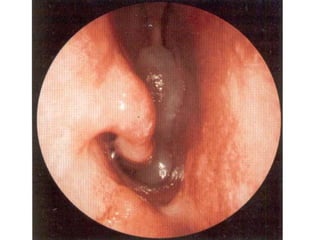

• Posterior Rhinoscopy : A Smooth Greyish Polypoidal mass occupying the

choana – AC polyp.

SIGNS • Patients havea distinctive hypo nasal voice. • Mouth Breathing. • Greyish pale glistening polypoidal mass can be seen through anterior rhinoscopy. It is insensitive and doesn’t bleed on touch. It is soft and mobile and can be probe all around except laterally. • Pale grey colour is due to poor blood supply but, in the presence of repeated trauma and inflammation, they may become reddened. The insensitivity is due to poor nerve supply. • Posterior Rhinoscopy : A Smooth Greyish Polypoidal mass occupying the choana – AC polyp. • A severe Eosinophilia may change the colour of the mucus from white to yellow or greenish yellow colour and was called allergic pus.